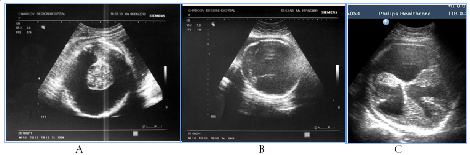

Obviously, that GPO of hydranencephaly and schizencephaly were unfavorable, wherein only bilateral schizencephaly was accompanied with clinically significant macrocrania (head circumference 430mm, it was above 95th percents of the average gestational circumference) (Figure 3). In case of hydranencephaly the liquor pressure did not increase and remained normal size of the fetal skull.

Figure 3Destructive brain lesions, 3cases.

Antenatal US signs of posterior fossa anomalies in 3 of 4 cases had favorable GPO, 2 of 4 had favorable СPO. That’s why, for such anomalies, antenatal prognosis could contradict with clinical postnatal catamnesis, and cause difficulties with accurately prognosing. In this way, abnormalities of Dandy-Walker spectrum are associated with indefinite perinatal and postnatal risk (Figure 4).

Figure 4US images of the fetuses posterior fossa structures and postnatal results, 4cases.

Figure 3 Destructive brain lesions, 3 cases. A) Hydranencephaly, total absence of cortical mantle and falx, saved diencephalon, hypothalamus and basal ganglia, wherein postnatal life was possible, by maintaining thermoregulatory functions, catamnesis - infant death in 3months. B) No structures of the brainstem, there are only remnants of supratentorial tissue, no sickle and cortical border, intranatal fetal death. C) Bilateral schizencephaly (type II, "open lip") with severe hydrocephalus and macrocrania, intranatal fetal death, clinically narrow pelvis, fetus-damaging operation.

Figure 4 US images of the fetuses posterior fossa structures and postnatal results, 4cases. A) Malformation or Dandy-Walker complex, agenesis of the cerebellar vermis and cystic expansion of the fourth ventricle in conjunction with facial and cardiac abnormalities, late neonatal death. B, C) Fetal US and brain MRI after birth in isolated Dandy-Walker variant, worms hypoplasia and mega-cisterna magna, favorable GPO and СPO. D) Mega-cisterna magna associated with facial and cardiac abnormalities, neonatal complications, long-term neurological disorders. E) Isolated mega-cisterna magna, favorable postnatal and long-term outcome.